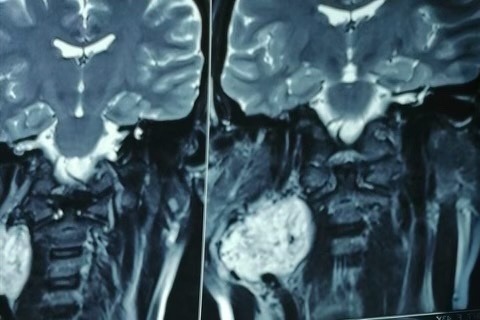

Hi, my name is Emily Sanchez. My aunt in Mexico, Miriam Sanchez, had COVID-19 back in October 2020, but was rushed to the emergency room because she was struggling to breathe. She was very sick for about a month before she started to recover. Soon after, my aunt noticed a bump forming on her neck that began growing and becoming painful to touch. The doctors discovered a tumor in between the two arteries that supply oxygenated blood from the heart to the brain, which is why she was having a hard time fighting the coronavirus. In the next few months, my aunt will need surgery to remove the growing tumor, or it is likely that she will have a stroke from the blockage of her arteries, preventing blood from reaching her brain. However, the procedure costs 1 million Mexican pesos, or around $50,000 U.S. dollars. My family and I ask that you help us raise $40k for Miriam's procedure as soon as possible so that she can get her tumor surgically removed.